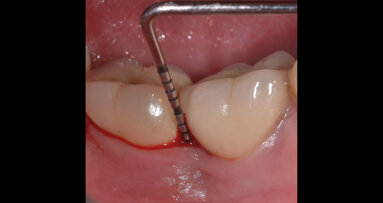

Si è proceduto ad acquisire una scansione CBCT dell’arcata nonché un’impronta digitale, utilizzando un repere su bite personalizzato per permettere il successivo matching delle immagini. Le sezioni CBCT evidenziavano creste di dimensioni ridotte (Fig. 2a) e un’accentuata concavità vestibolare in posizione 22 (Fig. 2b). Il progetto implantare ha previsto l’inserimento di due impianti B1ONE HIGH di dimensioni 3,2 x 12 mm in posizione 12 e 2,7 x 12 mm in posizione 22 (Fig. 3a). Gli impianti selezionati hanno piattaforma SMALL (Ø di 3 mm) e sono caratterizzati da una morfologia di spira (tipo HIGH) realizzata in conformità alle caratteristiche dell’osso24. Contestualmente all’inserimento implantare, la misurazione dell’integrale della curva torque-profondità ha dato conferma di stabilità dell’impianto25, 26. La progettazione implantare è stata quindi condivisa con un laboratorio specializzato (IDI Makers, IDI Evolution) per la realizzazione della corrispondente mascherina chirurgica per chirurgia guidata, con allestimento di piccoli lembi a spessore totale (Fig. 3b).

Fig. 2_Valutazione della disponibilità di spazio mesio-distale e di spessore dell’osso vestibolare; a) visione occlusale in corrispondenza degli elementi 12 e 22; b) immagine panoramica successiva a CBCT con sezione dell’osso vestibolare.